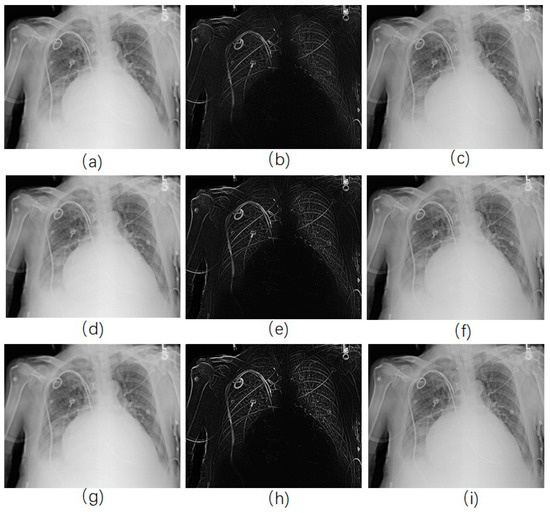

Once the edge-smoothed image is acquired by using RAD algorithm (Figure 2h), we subtract it from the original image to get the unsharp mask (Figure 2i), and then it is added to the original image (Figure 2j). Figure 2h shows that the edges in the image were smoothed and the noise was kept when the RAD algorithm was used, while the noise in Figure 2b were smoothed as well as the edges. In the final enhanced image, only the edges were enhanced in Figure 2j, while noise in Figure 2d, where the Gaussian smoothing method was used, was more obvious than that in the original image. Figure 2e shows the smoothed image acquired by using classical anisotropic diffusion. Only noise was enhanced in Figure 2g.

Figure 2. Image enhancement by use of different model. (a) Original image; (b) image smoothed by Gaussian kernel; (c) unsharp mask by subtracting (b) from (a); (d) enhanced image by adding (c) with (a); (e) smoothed image by use of traditional anisotropic diffusion; (f) Unsharp mask; (g) enhanced image; (h) smoothed image by use of reversed anisotropic diffusion; (i) Unsharp mask; (j) enhanced image.

Figure 5. CXR enhancement by use of reverse anisotropic diffusion (RAD) -based USM. (a,d,g) were the smoothed images with diffusion parameter 0.001, 0.02, 0.2, respectively; (b,e,h) were the corresponding unsharp masks to (a,d,g); (c,f,i) were the corresponding enhanced images.